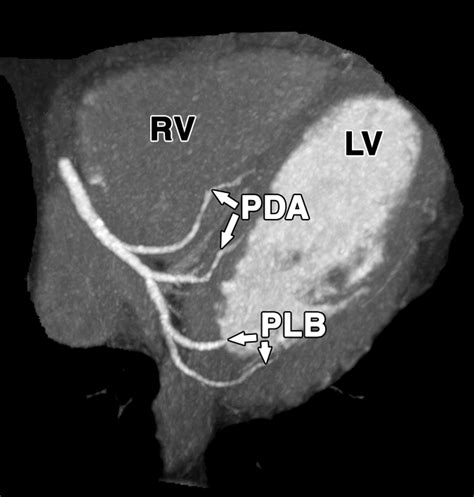

The Posterior Descending Artery is a branch of the right coronary artery, which originates from the aorta. It descends along the posterior interventricular groove, supplying blood to the posterior wall of the left ventricle and the posterior interventricular septum. This artery is crucial for maintaining the health of these regions, as it provides essential nutrients and oxygen to the cardiac muscle.

• Imaging Techniques: Advances in imaging technologies, such as cardiac MRI and CT angiography, are improving the visualization of the Posterior Descending Artery and other coronary arteries. This allows for more accurate diagnosis and treatment planning.